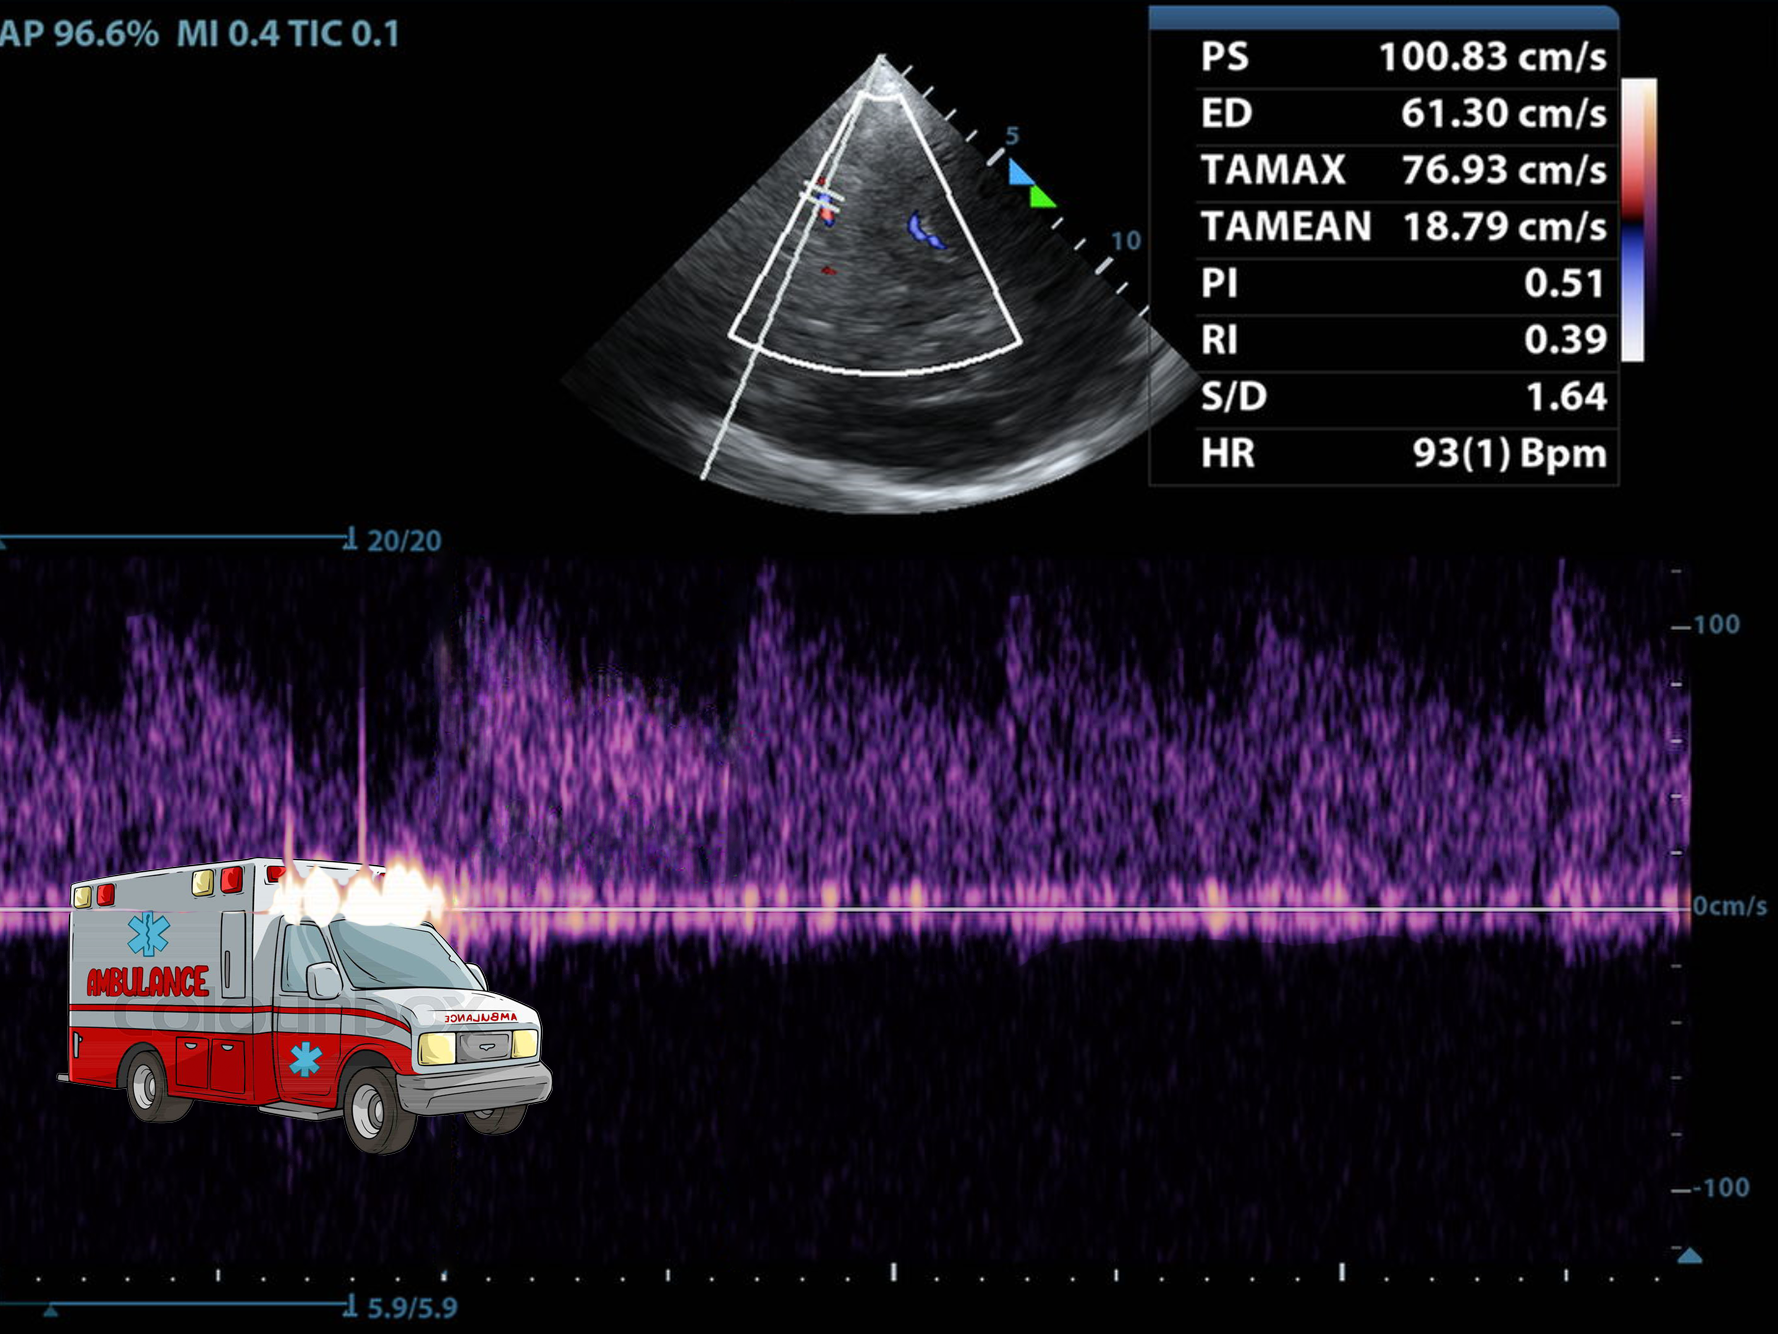

Making Waves: Adding Spectral Doppler

Transcranial Ultrasound in Resuscitation